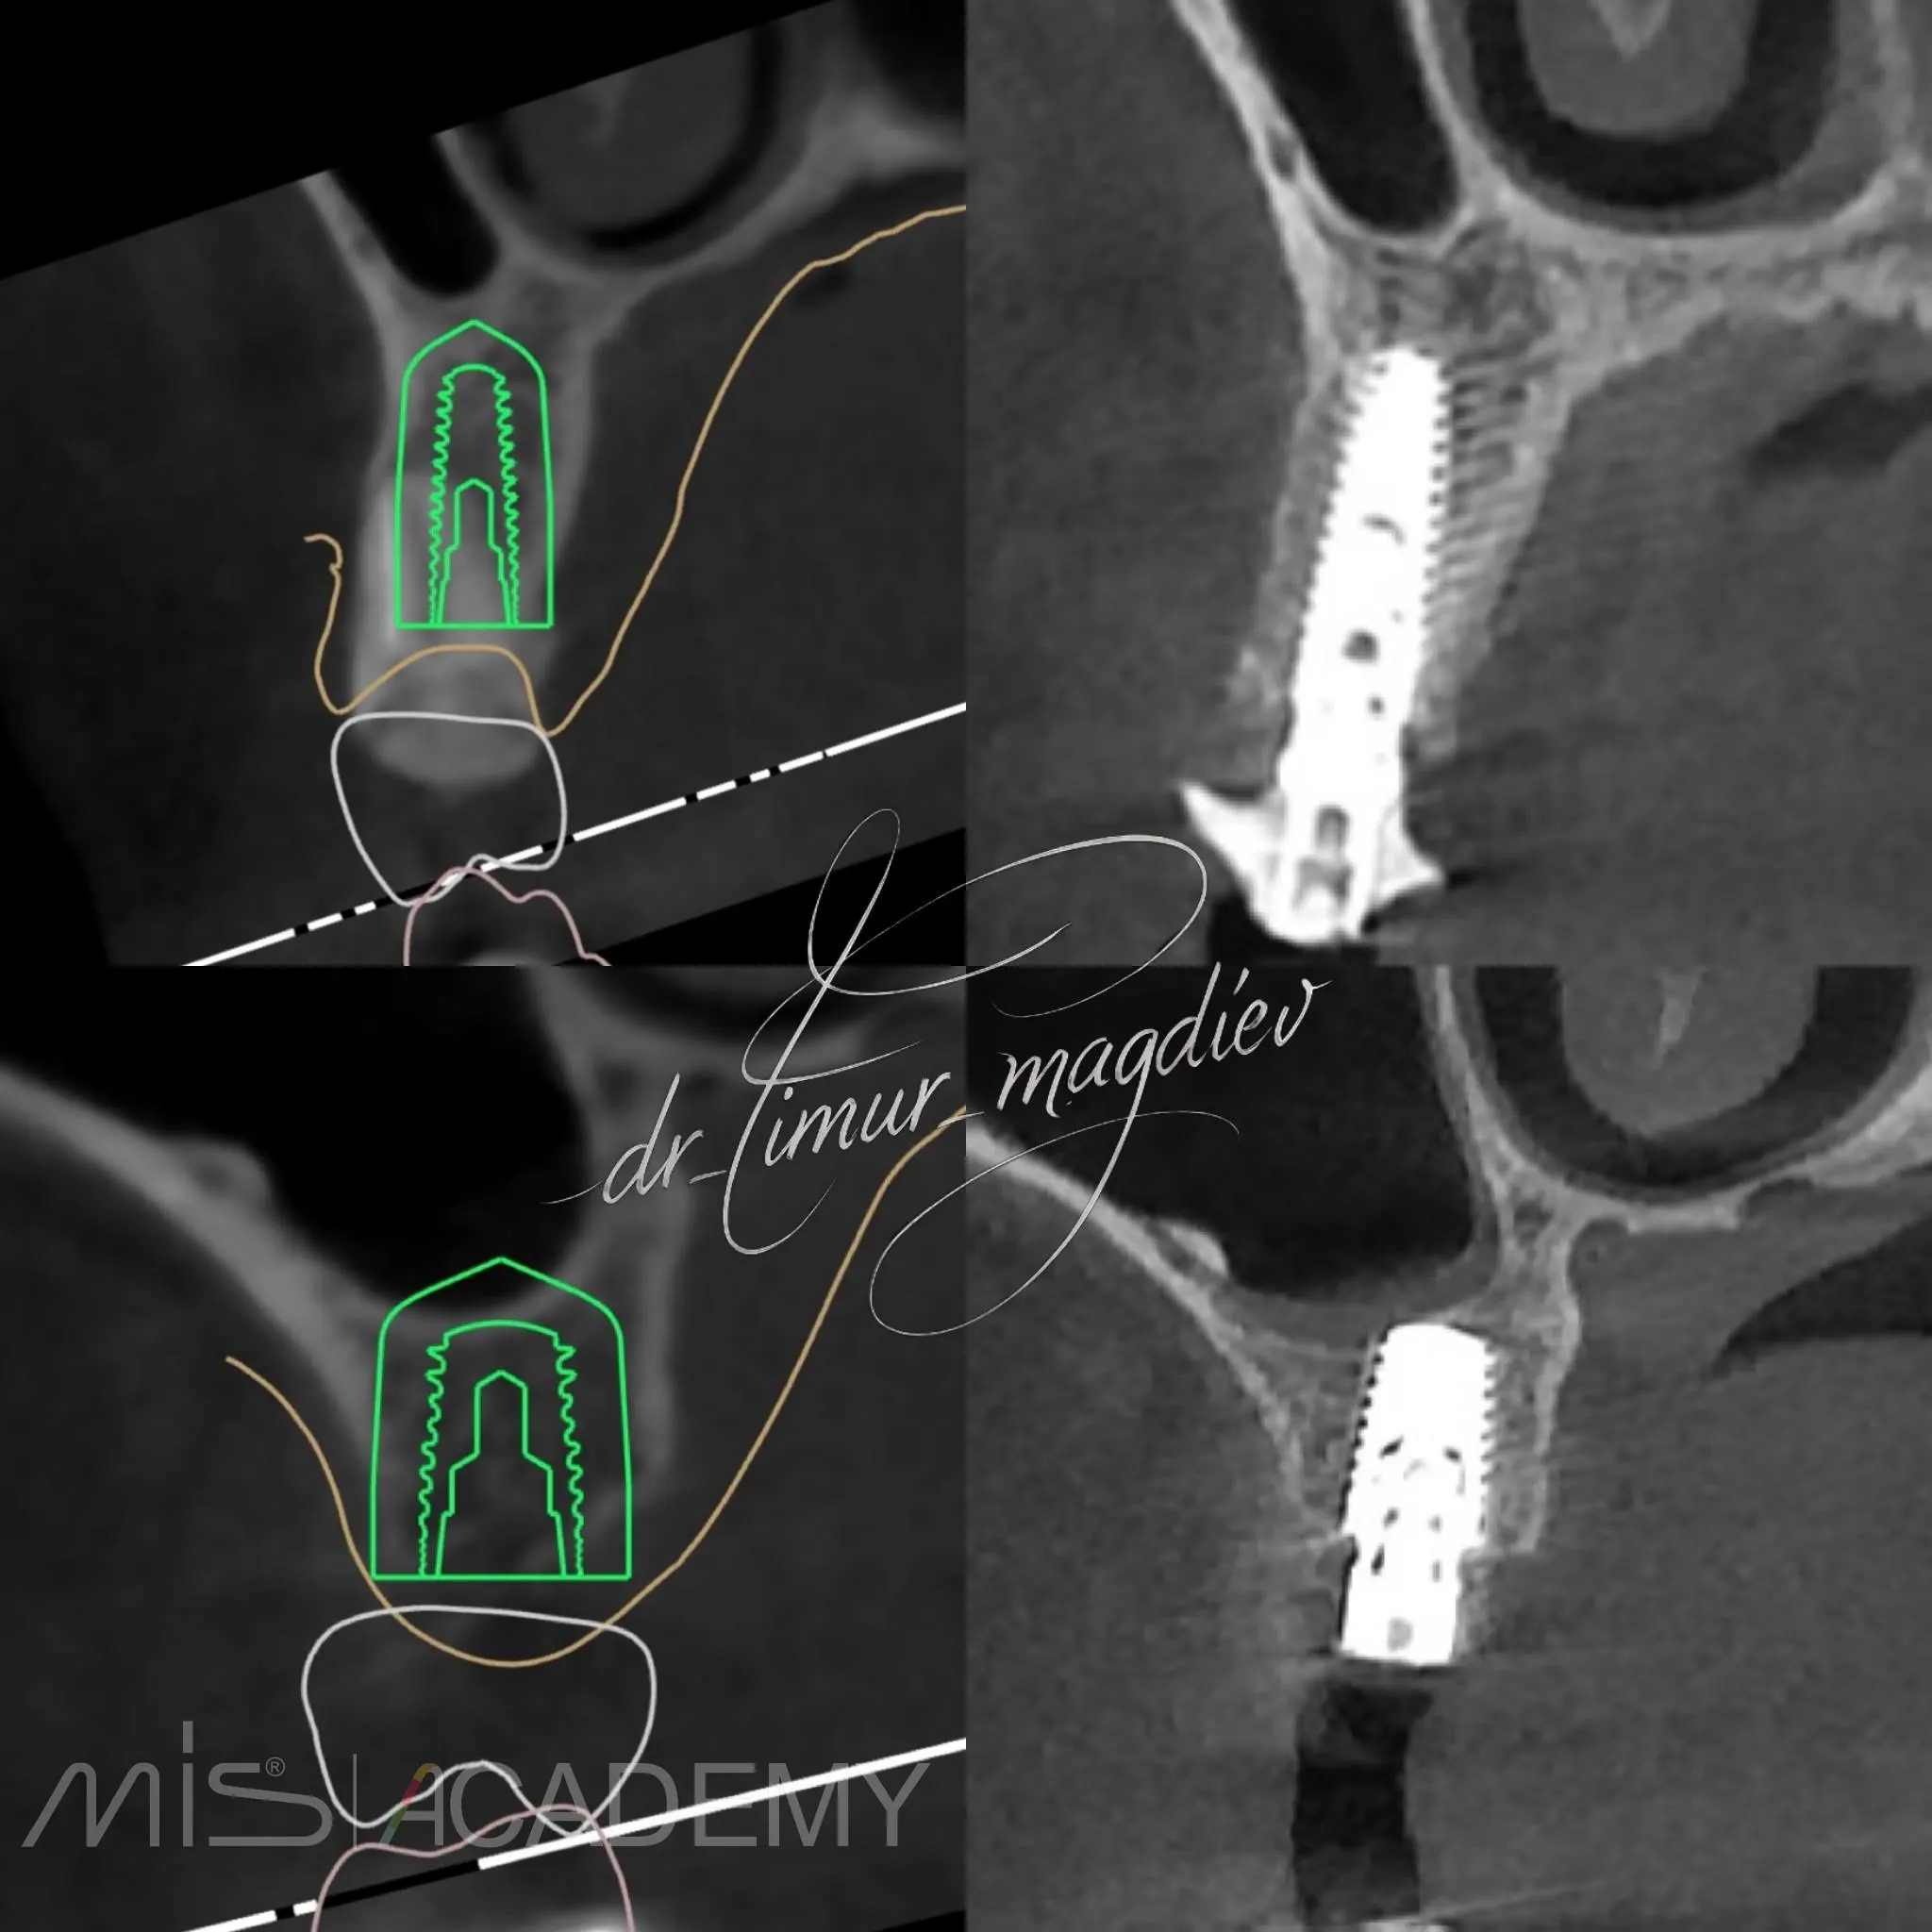

— Установка имплантатов MIS C1 + Connect в полном навигационном протоколе.

— 24 одномоментно IDR.

— 26 отсрочено.

Протезирование: Сергей Александрович Белоборотцев.